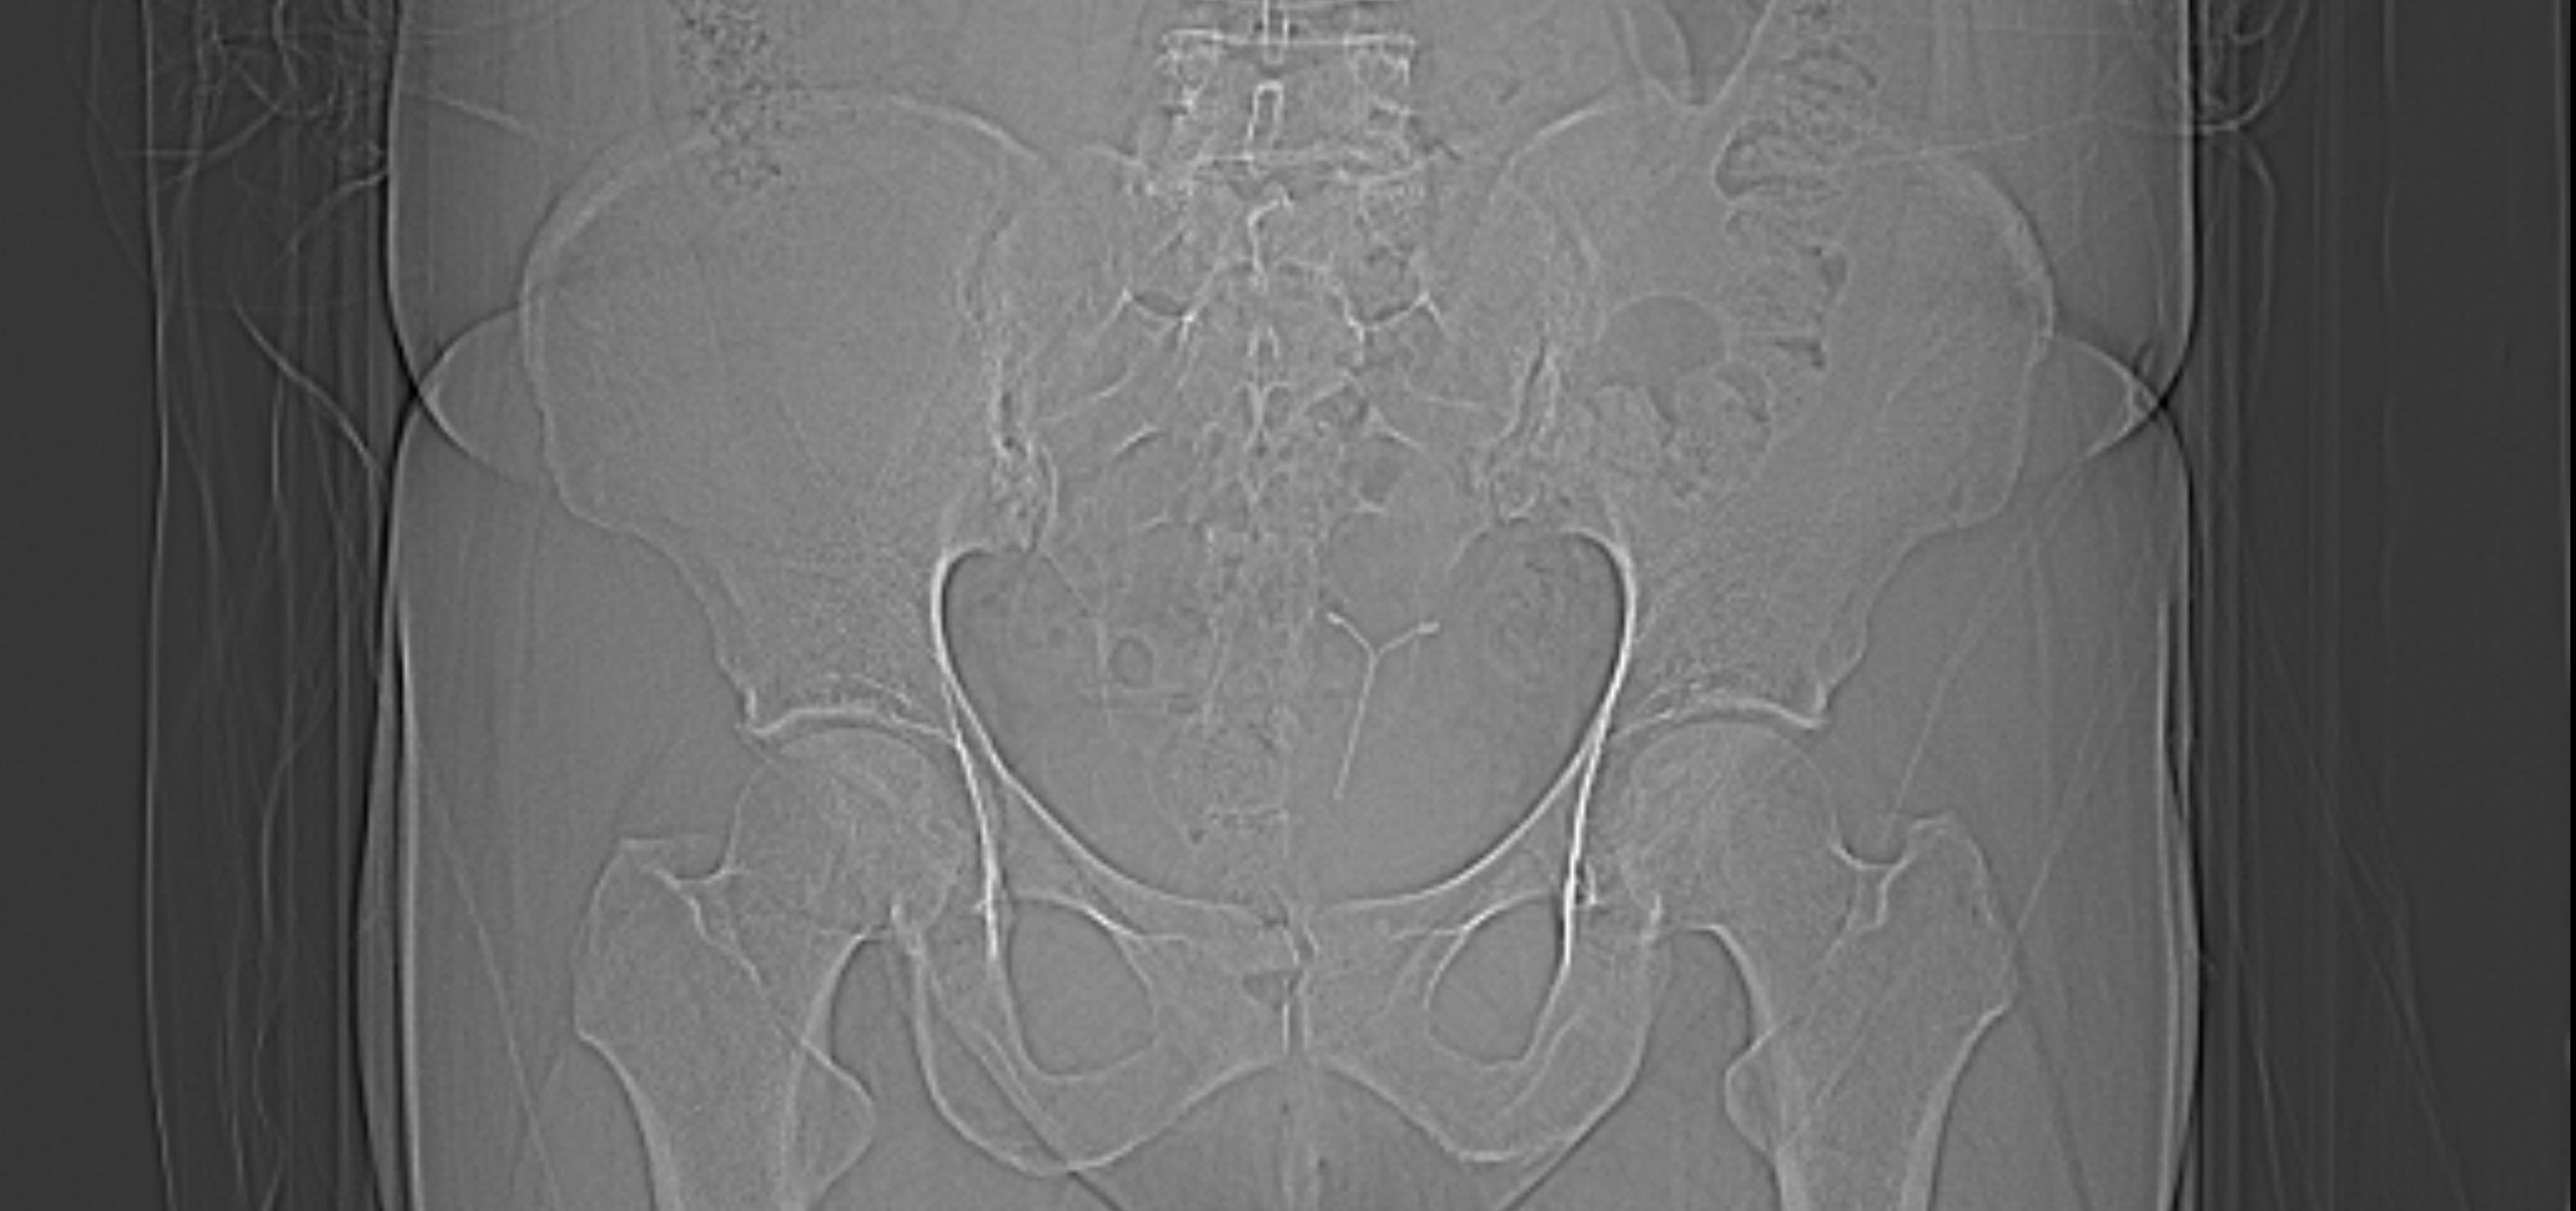

The purpose of the scan is to ascertain whether the coil has perforated the uterus. I already instinctively know that it has. He rolls a sheath onto the probe, squirts gel onto the long wand that looks like a dildo and jams it up inside me. I grunt in pain and swallow the sick that has risen into my throat. He is rough, impatient and fails to describe what he is doing to me. Silent tears roll down my face as he is inside me. I feel such a dark and primal shame and something in me wants it all to end, for me to end. It has been too much to bear. I know that I am being unceremoniously marched back to the other place and I don’t think I can face it again. As he pokes and jabs I look over at the chaperone. She is sat on the other side of the room in a curled up position, hunched shoulders, hands on her knees, eyes resolutely down. She may as well be wearing a T-shirt that says ‘See No Evil, Hear No Evil, Speak No Evil.” The probe is hastily pulled out and he tells me that there is no problem and that the consultation is over. I ask if it is the coil that could be causing the all the issues and the strangest thing happens. He tells me – categorically- that I have no coil fitted. I tell him that this is why this consultation is taking place- to find the coil. He says that he has no knowledge of this and that it was just a routine ultrasound. I explain that I absolutely know that I do have a coil and that’s what he was supposed to be looking for. He repeatedly tells me that there is no coil and that I am wrong. I lie there and wonder if I am going mad. But I know that I do have one- I felt the strings that morning- so I persist. Again, he says that there is definitively no coil and that I am wrong. I feel bone tired. The years of explaining, apologising, advocating- it’s enough now. But something in me is still fighting and I refuse to leave. Deep in me I know that it will only necessitate another gruelling visit and more penetration if I don’t get this sorted today. I insist that he does more tests to find the coil and he reluctantly sends me for an X ray and CT scans.

Matron arrives and she speaks to the doctor and then to me. When it is just the two of us she says that he had been unable to admit to me that he had been wrong and that instead of apologising he has doubled down into his position. They look at my CT scan and he finally accepts that there was a coil and I am told that it has perforated the uterus. He doesn’t apologise; instead he behaves like he knew there was a coil all along. If I had accepted his diagnosis that day then I would have left the hospital with a perforated uterus and no treatment plan. As it is, I email the surgeon to tell her about the perforation. This is her response.